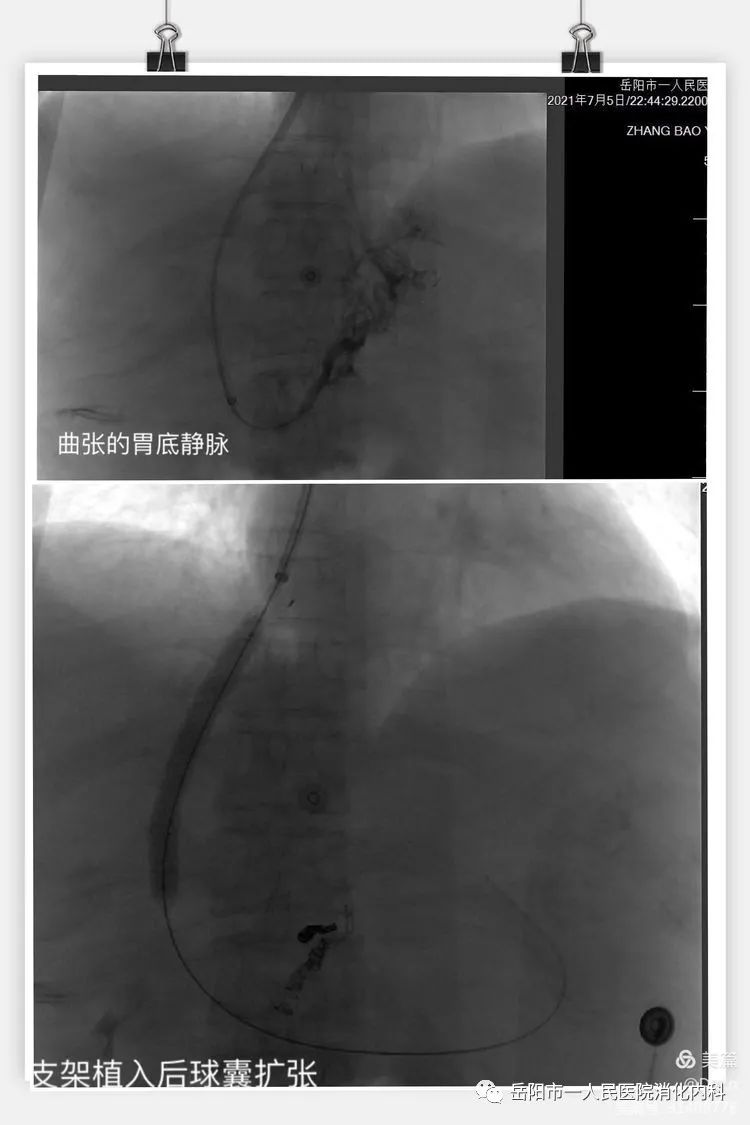

7月5日,在TIPS手术负责人胡关胜副主任医师及团队的充分准备下,成功为患者实施TIPS手术,手术总时长为2小时,其手术过程从门脉造影提示穿刺成功到支架造影,显示支架血流通畅,支架植入后进行球囊扩张, 支架前测得门脉压为50cmH2O ,支架后测得门脉压 为31cmH2O,并将曲张的静脉行栓塞治疗,到栓塞后曲张静脉消失,手术顺利完成。手术过程中,患者神志清醒,术后第2天,恢复正常饮食,正常下床活动,未出现呕血、黑便、肝性脑病等并发症,并于2021年7月9日复查门脉彩超提示支架血流通畅,7月12日出院。